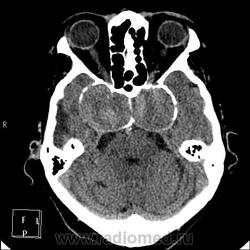

А контраст почему не делали? Больше похоже на тромбированные аневризмы

Неужели такие аневризмы? Бывает же! А сканы с контрастом есть?

Макроаденома гипофиза с интра-эндо-супра-и латероселлярным ростом,инвазией кавернозных синусов и зрительной хиазмы.

В первую очередь подумала бы о менингиоме бугорка турецкого седла или передних наклоненных отростков. Дифференцировала бы с краниофарингиомой но смущает форма.

Да простят моё нахальство уважаемые специалисты КТ. Я вижу тут огромные инкапсулированные узлы расположенные почти симметрично справа и слева от турецкого седла, которое разрушено узлом поменьше. Латеральные злы продавливают дно средней черепной ямы. По-видимому, здесь доброкачественная опухоль типа «аденома», исходящая из гипофиза и давно растущая. Обызвествление есть не только в капсулах узлов, но и в их толще (очаговое). При таких размерах узлов и косных разрушениях, нет сомнения, пострадали и зрительные нервы.

Цифровых и плёночных доказательств на руках нет. Опухоль диагностирована в 2004 году, размером "с вишню", дебютировала птозом века правого глаза, умеренной головной болью в лобной области слева и постепенным снижением зрения, катаракта. Пациентка с трезвом уме и превосходной памяти (на мой субъективный взгляд))). В выписке результаты КТ, МРТ: неоперабельная опухоль селлярно-параселлярной области с прорастанием кавернозных синусов, аневризма сифона внутренних сонных артерий. Цитологию НЕ брали.

Не совсем понятно, опухоль + аневризма или как?

Да, опухоль, в толще которой аневризма сифона ВСА. Причем с обеих сторон.

Аневризмы с обеих сторон или опухоль?

И то, и другое. Доказать без контрастирования не могу. Когда сама впервые увидела, анамнеза не знала, подумала о двусторонней аневризме. И не угадала.

Насчет опухоли у меня большие сомнения. То что седло растянуто, еще не показатель. Седло увеличивается в размерах даже при гипертонии,а тут такие аневризмы. Самой опухоли не видно, в просвете турецкого седла медиальные полюса аневризм. Ну впрочем не так это важно, интерес чисто теоретический, да и верификации видимо не будет. Спасибо большое за демонстрацию.

Случай-таки не верифицированный. Сочетание опухоли с аневрзмами - это очень странно. Боюсь, тут какая-то путаница.